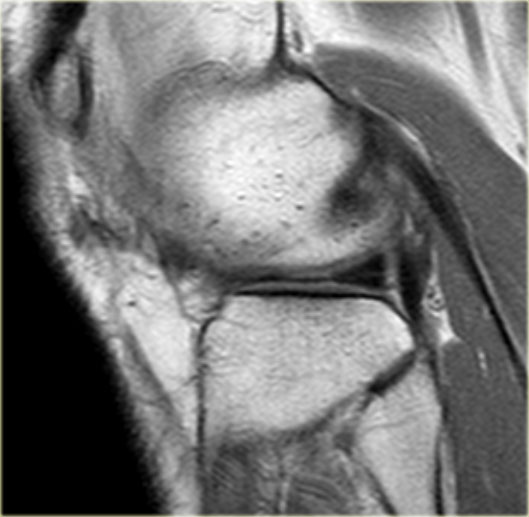

Bên trái là một trường hợp sụn chêm lật khác.

Lần này ở phía trong (medial).

Một phần sừng trước bị lật ra phía sau.

Chỉ một phần nhỏ của sừng trước được nhìn thấy ở phía trước.

Hầu hết các trường hợp sụn chêm lật xảy ra ở phía ngoài (lateral).

Dây chằng chéo trước (ACL) ngăn mảnh sụn chêm di chuyển hoàn toàn vào hố gian lồi cầu.

Trên hình ảnh mặt phẳng coronal, trước tiên sẽ thấy sừng trước to và phồng lên.

Ở phía sau sẽ thấy sừng sau rất nhỏ.